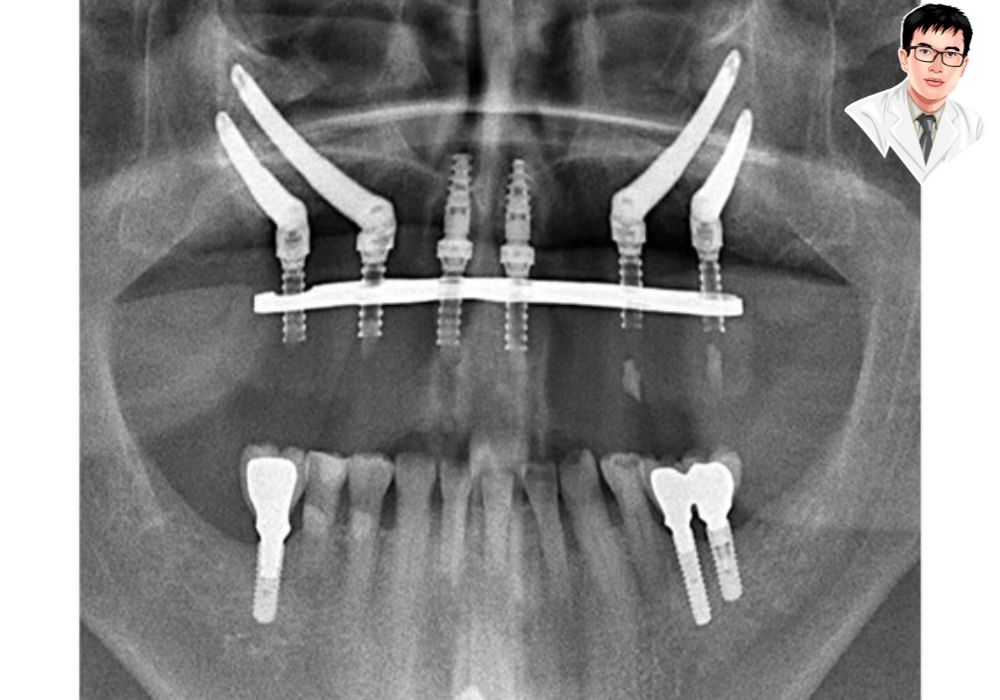

X-quang implant Zygoma hai bên – phù hợp với bệnh nhân tiêu xương hàm nặng.